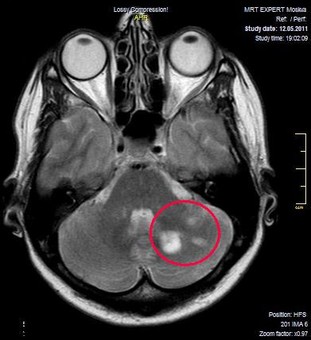

| Пример ремиелинизации при рассеянном склерозе. Пациентка с рассеянным склерозом была обследована на одном и том же МР-томографе до и после 4х-месячного курса лечения. | |

| ДО ЛЕЧЕНИЯ | ЧЕРЕЗ 4 МЕСЯЦА ОТ НАЧАЛА КУРСА |

- По изменениям на МР-томограммах. Это не очень надежный критерий. Конечно, уменьшение размеров очагов демиелинизации на МРТ – очень позитивный показатель. Но мы видим множество пациентов с хорошими результатами восстановительного лечения и неизменной МР-картиной.